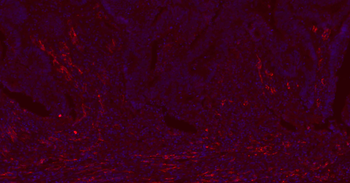

IF analysis of rat kidney tissue using anti-CD31 (dilution of primary antibody at 1:100)

IF analysis of rat lung tissue using anti-CD31 (dilution of primary antibody at 1:100)

Immunofluorescence analysis of rat skin tissue using CD31 antibody (dilution of primary antibody - 1:100)